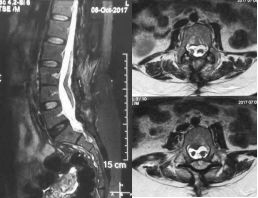

术后5个月影像学复查见骨棘切除满意,脊髓无卡压及粘连,患者主诉腰痛症状明显减轻,大便费力缓解,仍残留有小便困难,下肢肌力恢复至IV级。